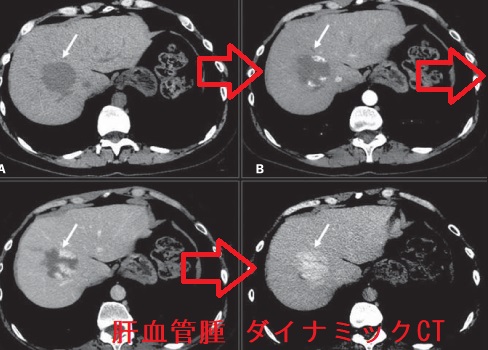

肝血管腫で甲状腺機能低下症

肝血管腫は甲状腺ホルモンを不活化する3型脱ヨード酵素(DIO3)を発現し消費型甲状腺機能低下症に。LT3製剤・LT4製剤で治療。肝細胞癌でも甲状腺機能低下症に。レンビマ®(レンバチニブ)は根治切除不能な分化型甲状腺がん(乳頭癌・濾胞癌)に適応ある分子標的薬で切除不能肝細胞がんに投与すると、甲状腺癌では報告の無かった潜在性甲状腺機能低下症、顕在性甲状腺機能低下症、破壊性甲状腺炎の副作用。甲状腺濾胞癌・濾胞型甲状腺乳頭癌は孤立性肝転移。甲状腺髄様癌・甲状腺カルシトニン陰性神経内分泌腫瘍の肝転移もある。肝膿瘍から甲状腺膿瘍が生じる。